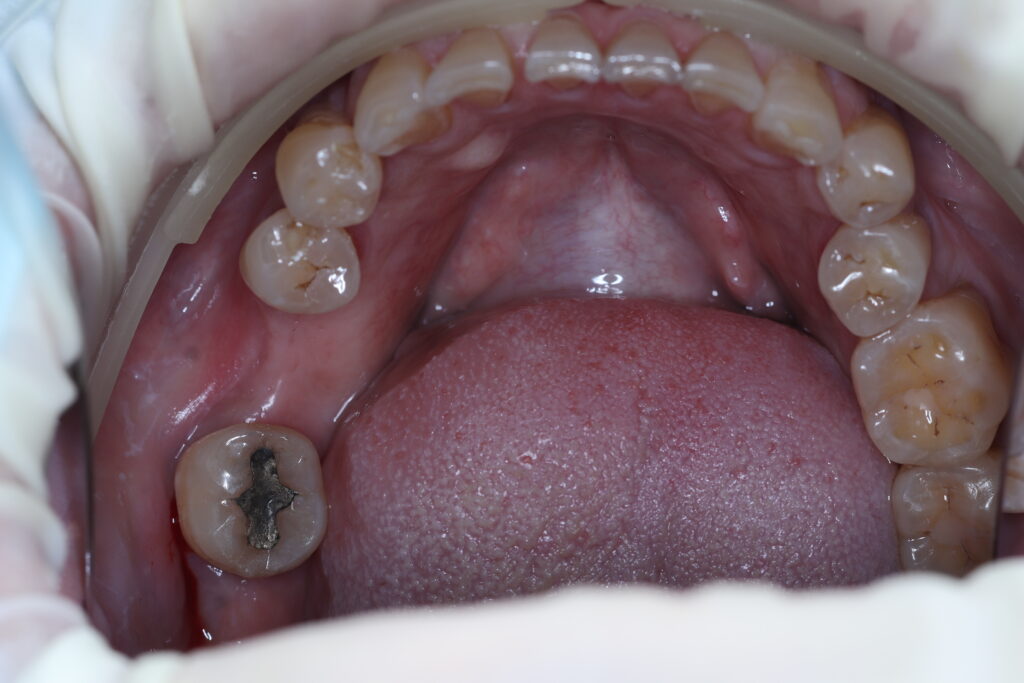

ผลงานบางส่วน ของทีมทันตแพทย์ของคลินิกเรา โดยได้รับอนุญาตให้เผยแพร่ ด้วยความเต็มใจจากผู้ป่วยขอบขอบคุณผู้ป่วยทุกๆท่าน

ก่อนทำรากฟันเทียม